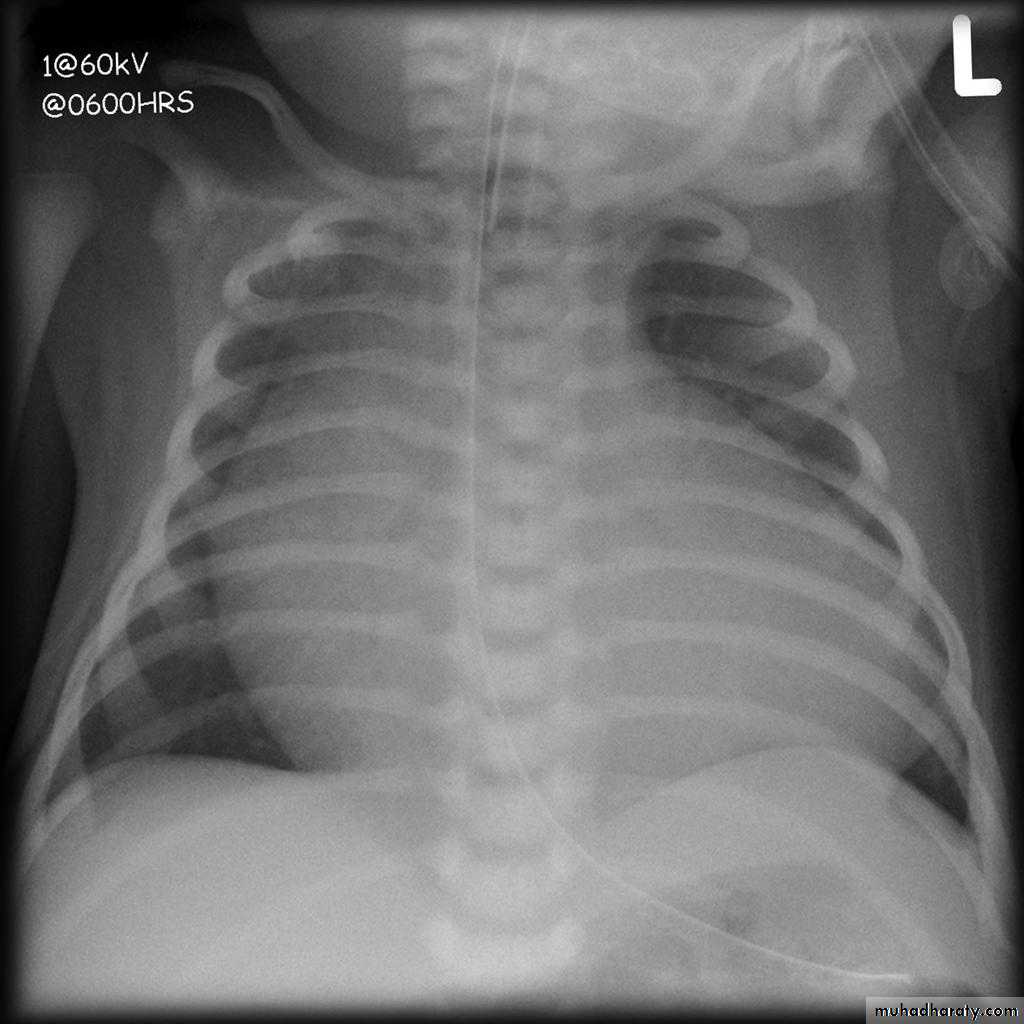

Plain film "boot shaped" heart ( TOF )

Plain films may classically show :

1. "boot shaped" heart with an upturned cardiac apex due to right ventricular hypertrophy and concave pulmonary arterial segment.

2.Pulmonary oligaemia due to decreased pulmonary arterial flow.

3.Right sided aortic arch is seen in 25%.

TOF